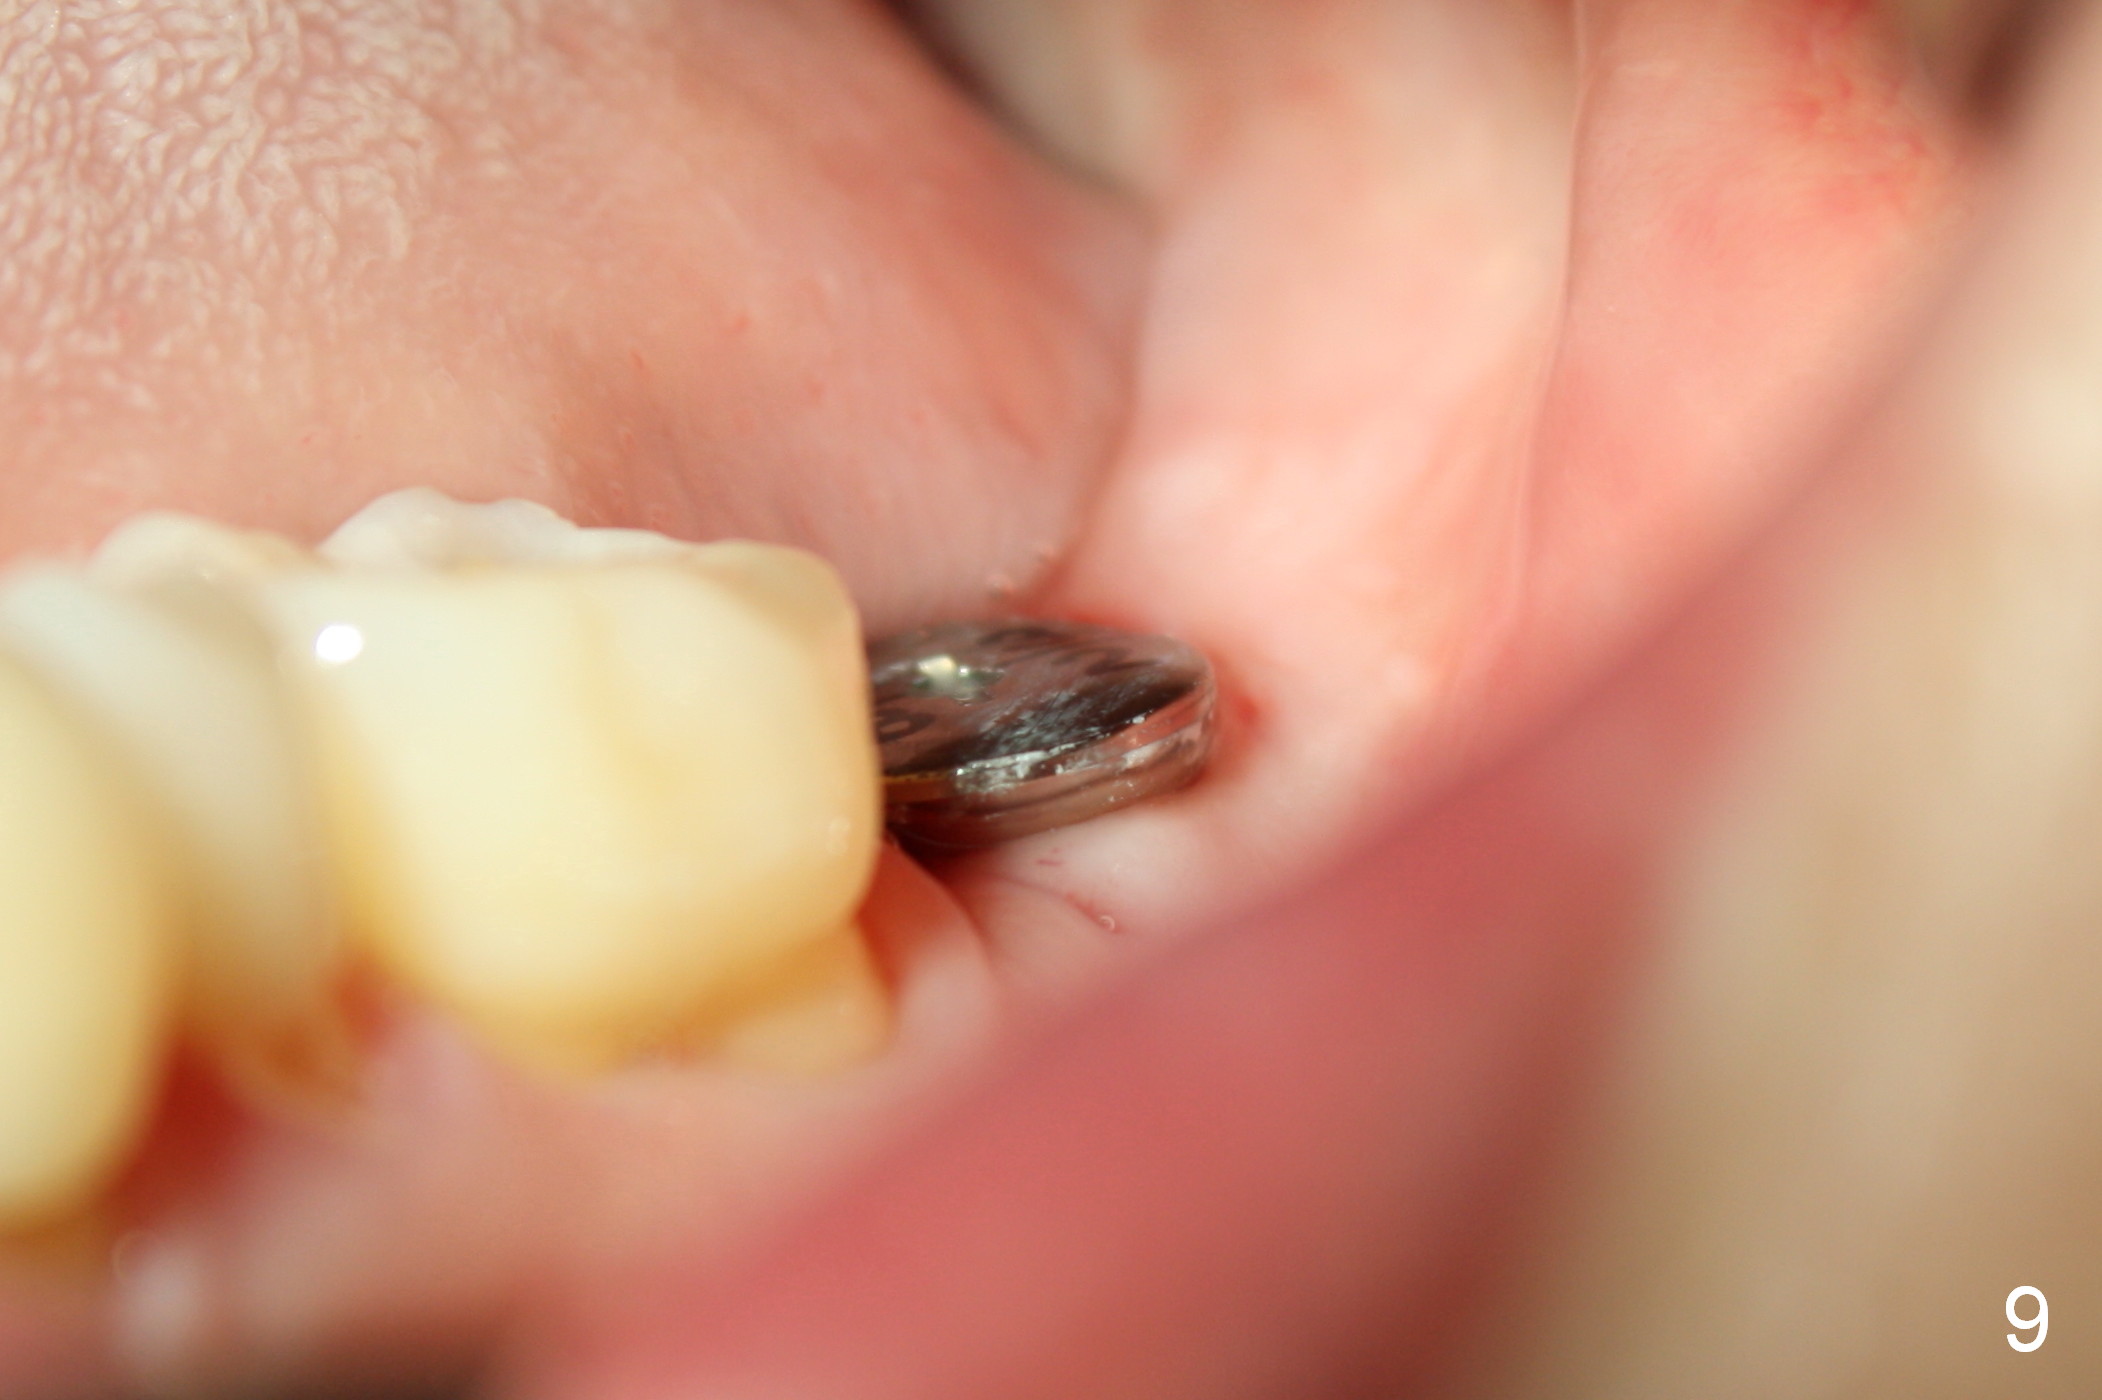

A 48-year-old lady is a dental phobic, requesting extraction of the lower left 2nd molar (Fig.1).   She returns for implant placement 9 months post extraction (Fig.2).  The ridge is mildly to moderately atrophic.  It appears that a 5x12 mm implant is appropriate for the site (Fig.3).  For safety, osteotomy is initiated at the depth of 10 mm; it appears that there is enough height for a 12 mm implant (Fig.4).  The depth is controlled by drill stopper (Fig.5 S).  Finally a 5x12 mm implant is apparently safely placed (Fig.6).  A healing abutment is placed and the incision is sutured with 4-0 Chromic gut (Fig.7).  Perio dressing is applied around the healing abutment for wound protection (Fig.8).  It appears that the healing abutment (Fig.8': *) helps stabilize the perio dressing, which remains in place 1 week postop.  When the perio dressing is removed, the wound around the healing abutment is healing (Fig.9).  There is no bone loss around the implant 3 months postop (Fig.10 (H: healing abutment), or 16 months postop (i.e., 9 months post cementation, Fig.11,12).  The patient complains of pain when she chews with the implant crown, but pain stops whenever she does not bite.  Percussion does not elicit any discomfort.  The gingiva is healthy.  There is possibility of the buccal plate being thin or the lingual plate being perforated in the submandibular fossa.  If the discomfort remains the same next 6 months, CBCT will be prescribed.